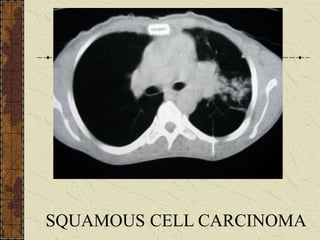

Squamous cell carcinoma

with calcification